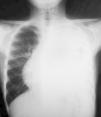

Las pruebas complementarias realizadas determinaron la existencia de una masa de gran tamaño en el mediastino anterior izquierdo, con un desplazamiento de las estructuras vecinas y un colapso casi completo del pulmón izquierdo (figs. 1 y 2).

Tomografía computarizada de tórax con contraste: hemitórax izquierdo de mayor tamaño que el derecho, ocupado por una masa que cruza la línea media en el espacio retoresternal y desplaza los grandes vasos, el corazón y la aorta, descendente hacia el hemitórax derecho. Rodea al pulmón izquierdo, que se ve colapsado en la parte media del hemitórax.